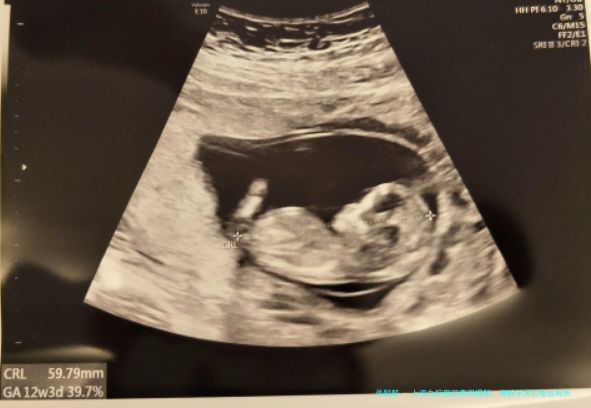

在上海九院采卵非常的快捷,全过程就15分钟左右,这是做试管婴儿移植的必经过程,众人全面的认识后就不会发生很大的惧怕感,下面是上海九院取卵步骤,有兴趣的可做了解。

1在取卵当天病人最佳自己使用生理盐水进行1个容易的洗脸刷牙; 2在手术前患者先排尿,保持膀胱身在排空状况,这样更利于取卵; 3在进入手术室后,为了防备感染,医生会对病人外阴及阴道进行严格的消毒和冲刷; 4消毒做到后,取卵时医生会对患者进行探针穿刺,起先将探头上牢固一根太长的穿刺针,然后将穿刺针尾端连接负压力吸取器; 5设备准备做到后医生会把探头置入女性阴道,B超机显现出卵巢模样及卵泡位子大小,使穿刺针快速刺入卵泡腔内,开启负压吸取器,抽吸卵泡液,卵子只在所抽取的卵泡液中; 6最终医生会把取出的卵泡液送到胚胎培育室工作台,待实验室人员检卵。